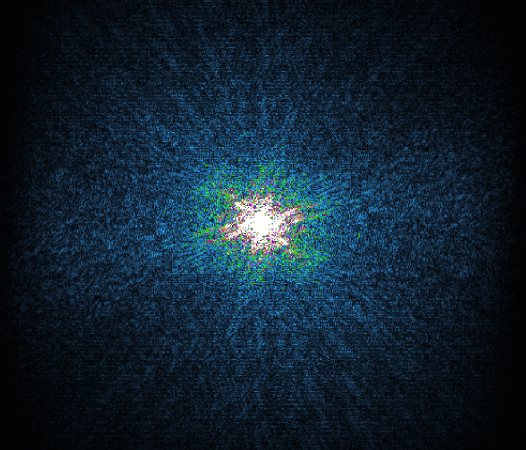

The Compressed SENSE reconstruction then uses iterative, knowledge-based algorithms to fill in the empty lines in k-space (bottom left). This removes the artifacts while keeping the final image fully consistent with the acquired data (bottom right).

K-space compressed sense